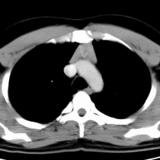

Case 8c Thymoma CT

Date: 03/27/2009

Views: 15482